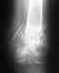

снимок 25.08.11, после которого мне сказали, что нужно полностью гипсовать руку на 2 месяца!

Напомню, до этого стоял аппарат с февраля. Боюсь, что руку уже никогда не разработаю. Кисть не крутится, ну пока и не пытаюсь.